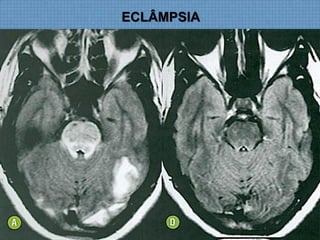

ECLÂMPSIA

ACHADOS DE IMAGEM

• RM:  Determina diagnóstico e estima prognóstico;

– T1:Hipossinal em topografia subcortical parietoccipal, com

rara impregnação puntiforme pelo Gd;

– T2/FLAIR: Hiperssinal digitiforme parietocciptal, podendo

estender-se para as regiões cerebrais anteriores, além do

NB;

– SWI: Permite diagnóstico de hemorragia de permeio 

Hipossinal;

DIFUSÃO!

Usualmente normal  Só edema vasogênico;

Se restrição  Dano cerebral irreversível;